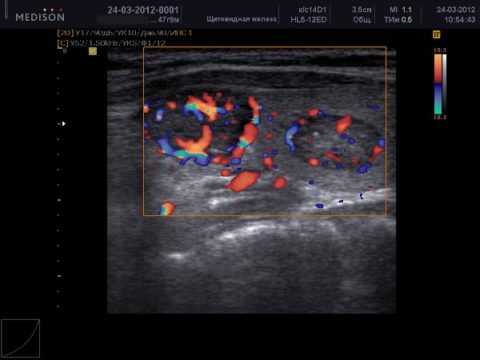

ЦДК

Данное исследование позволяет выявить, в каком направлении проходит кровоток. Разные направления движения обозначаются разными цветами: синим и красным. ЦДК позволяет разделить жидкостные новообразования и активно функционирующие кровеносные сосуды. Его результат служит для уточнения диагноза.

Палитра изображения красно-коричневая либо красно-оранжевая. Чем большее количество частиц движется, тем ярче цвет картинки. Большая интенсивность кровотока указывает, в большинстве случаев, на развитие воспаления. Коричневый цвет означает малое количество частиц, находящихся в движении.

Обычное УЗ-исследование и допплерография одного и того же патологически измененного фрагмента щитовидки